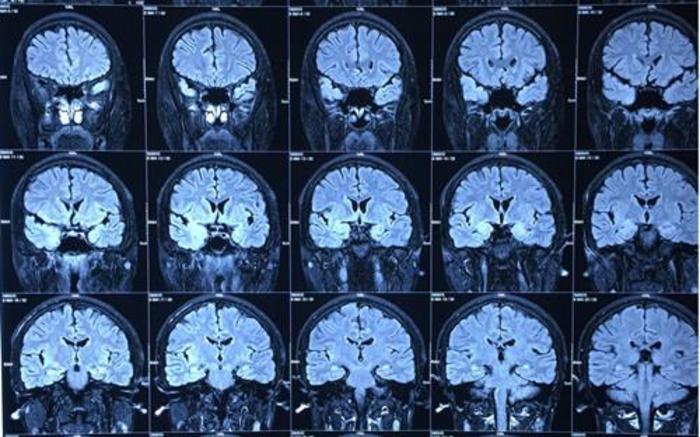

海马解剖及影像学评估

海马高清磁共振解剖及扫描方法

扫盲海马mri该如何扫描

影像基础:海马mri解剖分享讲解,2分钟学会!